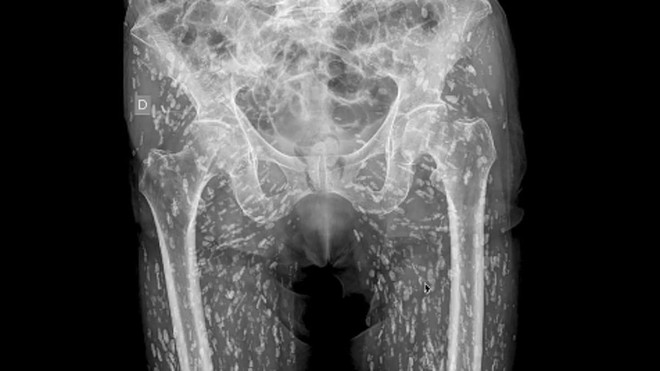

Ảnh chụp X-quang phần hông của bệnh nhân. (Ảnh: Dailymail)

Kết quả cho thấy bệnh nhân bị gãy xương hông. Đáng nói, bác sĩ còn phát hiện thêm rằng quanh các mô mềm ở phần hông và đùi có chi chít đốm trắng. Bệnh nhân thực hiện thêm một số xét nghiệm cần thiết khác, kết quả cho thấy bệnh nhân mắc sán dây lợn.

Bác sĩ Sam giải thích: “Bệnh nhân được chẩn đoán mắc sán dây lợn. Các đốm trắng chi chít trong phần mô mềm ở hông và đùi là nang ấu trùng của sán dây lợn”.

“Các nang sán này có thể di chuyển khắp cơ thể. Với trường hợp của bệnh nhân nam kể trên, các nang sán di chuyển nhiều ở các mô cơ và mô mềm ở hông và chân”, bác sĩ Sam nói tiếp.